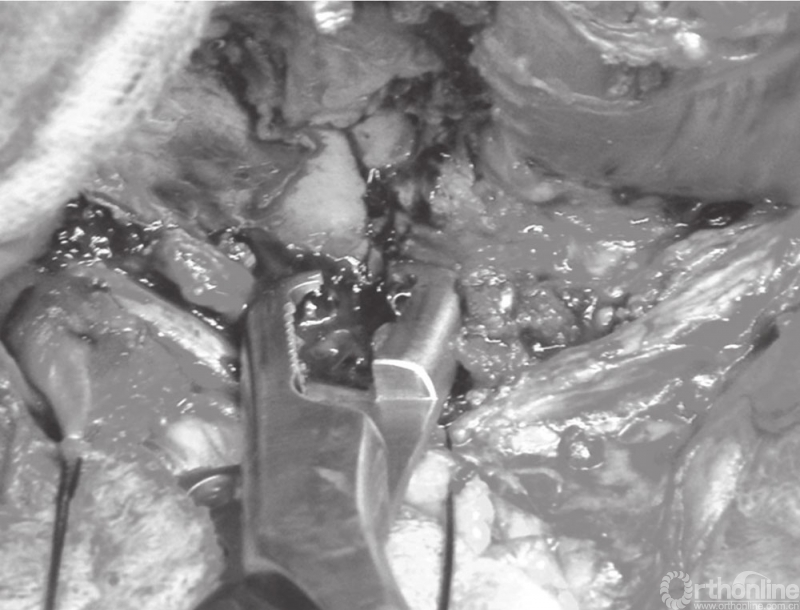

利用2枚螺钉联合骨盆复位钳完成后柱

有种有效的复位策略是在骨折的两侧分别打入一枚螺钉,通过相对应的复位钳进行辅助复位固定。随着复位钳逐渐夹紧,骨折移位被纠正并复位(图24.17)。骨折平移和旋转移位也可通过这种组合复位办法进行纠正。